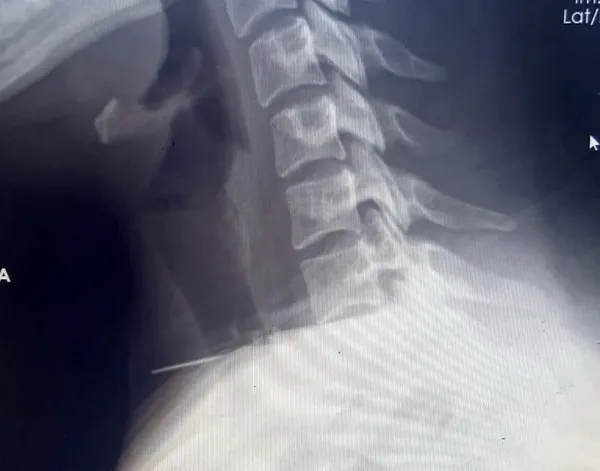

Hastanın boynunda iğne bulunduğu şikâyetiyle hastaneye başvurmasının ardından yapılan radyolojik incelemeler ve klinik değerlendirmeler sonucunda, iğnenin boyun bölgesini tamamen geçtiği tespit edildi. İğnenin, karotis arter ve juguler ven gibi önemli damarları içeren karotis kılıfı yakınında, boynun derinliklerine ilerlediği belirlendi.

Hastanın acil olarak ameliyata alınmasına karar verildi. Genel anestezi altında gerçekleştirilen ve yaklaşık bir saat süren ameliyatla, büyük damarlar ve sinirlere birkaç milimetre mesafede bulunan 3 cm uzunluğundaki iğne başarıyla çıkarıldı. Ameliyat sonrası süreci sorunsuz atlatan hasta, ertesi gün taburcu edildi. Uzmanlar, bu tür vakaların nadir görüldüğünü belirterek dikkatli olunması gerektiğini vurguladı.